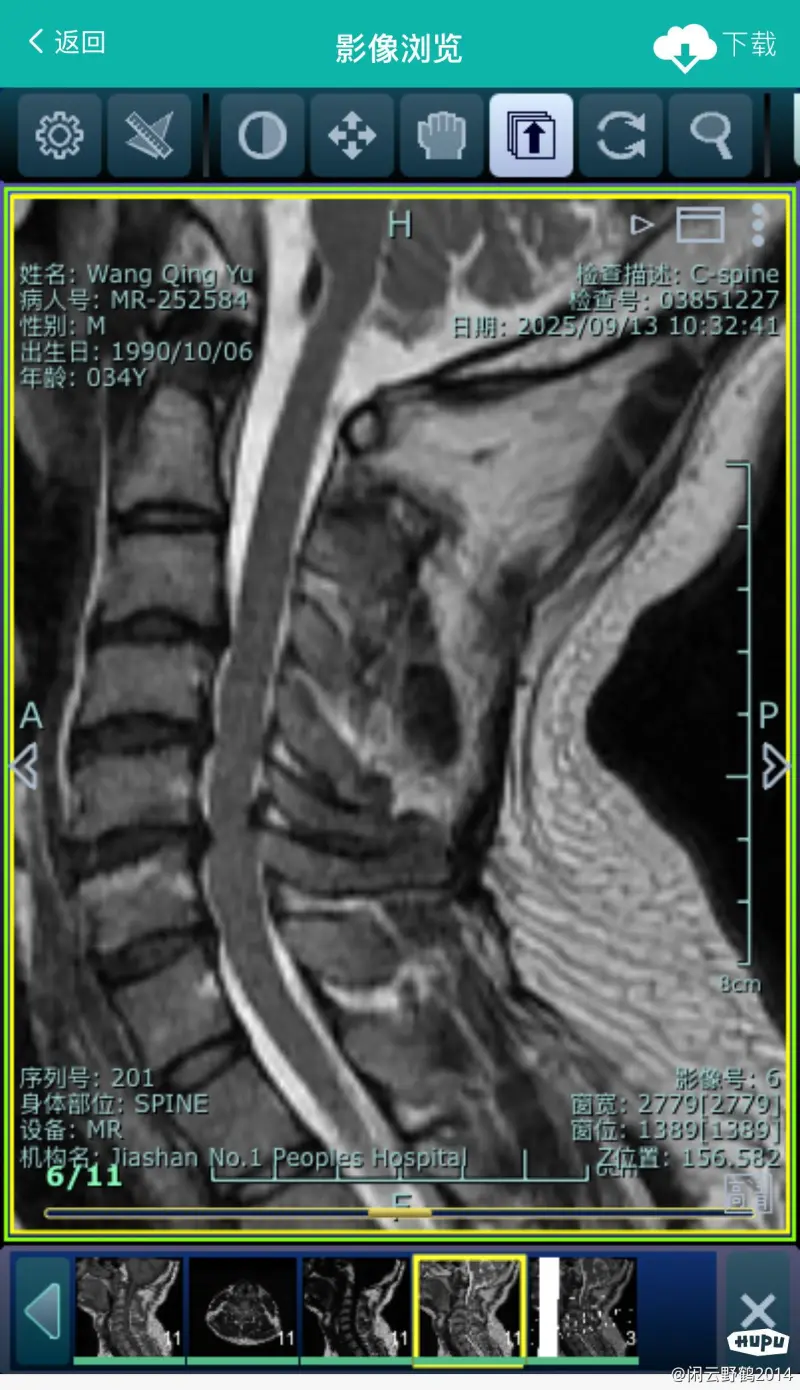

前不久晚上手麻 核磁共振一做 麻蛋了 什么都不突出,颈椎突出了 医生说这辈子极大概率免不了要挨一刀。有没有大神治疗经验传授

关于颈椎这个话题,我可能是最有资格说话的,我做了三次颈椎手术,脖子前面一次,脖子后面两次,我的颈椎上打着4个钢板,12根钢钉,一个金属网兜,我要把我的片子拿出来让你们看,能把大多数人吓得翻个跟头,很多人第一反应这他妈是机器人的颈椎吧?全是铁